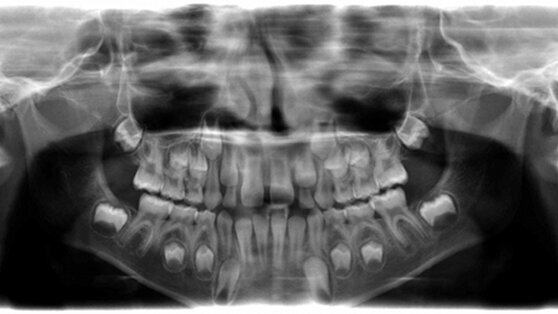

Une jeune patiente a été adressée au cabinet, souffrant d’une molaire inférieure. La radio a indiqué une lésion sur les deux racines, avec les canaux mésiaux pas encore pleinement formés, en ce qui concerne la longueur et le diamètre (Fig. 1).

Après discussion du cas avec les parents et l’explication de la nouvelle technique, j’ai ouvert la molaire en conditions très aseptiques. La racine distale a montré des signes de léger saignement, donc la pulpe était relativement vitale. Les racines mésiales n’ont pas montré de signes de saignement, mais la pulpe résiduelle était clairement visible au microscope. Après irrigation copieuse à la chlorhexidine dans les racines mésiales et distales, une solution de SmearClear (SybronEndo) a été instillée, et une activation passive avec une lime K N°10 a été exécutée dans les canaux mésiaux, avec juste un peu de saignement. De l’eau distillée a été employée pour rincer tous les produits chimiques et une pâte antibiotique duelle a été placée. Ensuite, un ionomère de verre a été placé en technique sandwich, sous un composite (Fig. 2). La patiente ne s’est plainte d’aucune douleur, juste un léger inconfort.

J’ai contacté les parents de la patiente, à plusieurs reprises, pour leur proposer un contrôle mais malheureusement, ils n’ont pas répondu. Après 18 mois, j’ai reçu un appel d’eux, me disant que la patiente ressentait un certain désagrément. Je lui ai immédiatement donné un rendez-vous et je fus étonné de voir à la radio, une formation complète des racines mésiales et la fermeture de la racine distale (Fig. 3). La raison de la gêne était une fente coronale avec une perte d’une partie du composite. La fuite coronale était donc le problème principal. Les racines étaient alors complètement matures et j’ai donc effectué un traitement de canal radiculaire conventionnel, en utilisant les TF (Twisted Files : limes torsadées) pour un traitement crown-down, et un agrandissement apical jusqu’à la taille 45 en mésial, et 50 en distal, avec des limes K3, de conicité .04. Les canaux radiculaires ont été scellés en utilisant le RealSeal (SybronEndo ; Fig. 4). La patiente a été envoyée chez son dentiste pour la restauration molaire.